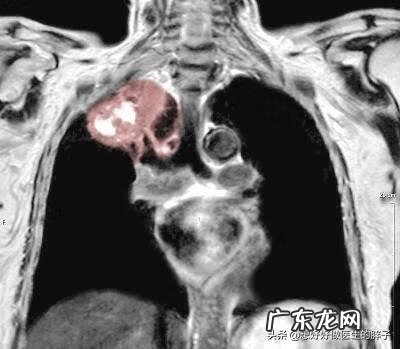

对于肩痛千万不要掉以轻心,一定要去医院进行相关的检查,而且作为医生也应该要多想、多考虑,尽量排除掉一些可能诱发肩痛的严重问题,尽力避免误诊影响患者的治疗,个人觉得医生多想点儿不为过,即使考虑属于过分担忧,但是也比误诊好!